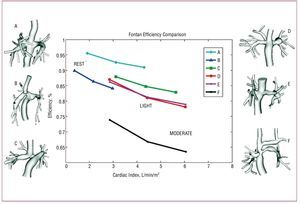

Recently, Marsden et al proposed a multiple parameter approach to evaluating Fontan performance.14,16 These studies also incorporated key modeling advances including respiration effects, simulated-exercise, unsteady flow conditions, physiologic pressure levels and particle tracking methods. Using patient-specific models derived from image data, comprehensive simulations were performed for 6 Fontan patients at rest and under 2 levels of simulated exercise conditions. For each patient, several performance parameters were computed, including energy efficiency, IVC and SVC pressure levels, WSS and quantitative data on the distribution of IVC flow to the left and right pulmonary arteries. For each of these parameters, patients were ranked in order of best to worst performance.

Figure 2 shows 6 patient-specific Fontan models (labeled A-F) and their simulated energy efficiency at rest and exercise. The results show a striking decrease in efficiency with exercise, and a wide range of performance among patients. Simulated pressures were well matched to catheterization data, but low Fontan pressure did not correlate with high efficiency.

Figure 2. Energy efficiency comparison from patient-specific modeling of 6 Fontan patients at rest (first data point) and two levels of exercise (second data point).

The results of this study demonstrated that different performance parameters produced different rankings when ordering patients from best to worst performance. Thus, a single simulation-based parameter (such as energy dissipation) is not likely to hold all the answers to improving Fontan performance. The multiple parameter approach illustrates the fact that we still do not know what defines "good" or "bad" Fontan performance, and that we will not have a quantitative answer to that question until multiple parameters are quantified and validated against clinical outcomes.